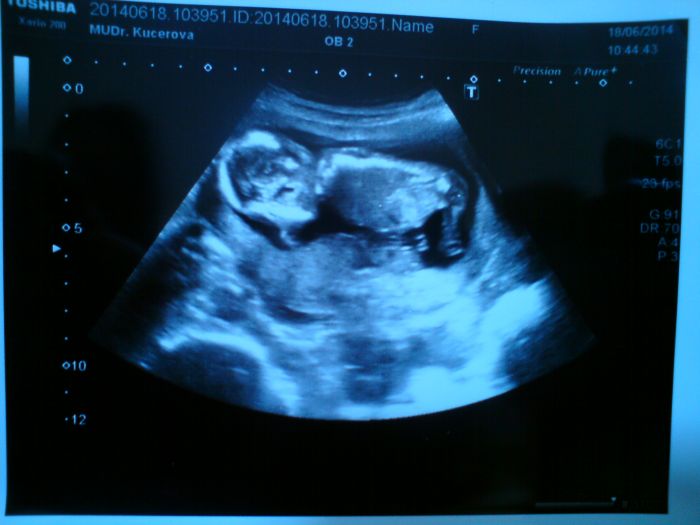

miminko je zdravý

pohlaví ještě nevím...vystrkovalo pořád prdelku a krčilo nožičky tak to nebylo vidět...brala mi krev na triple test tak si mám příští týden zavolat a mám se za 14 dní objednat na srdíčko na velký UZ...jsem šťastná že je vše v pořádku

[569668] Ahoj Jani, mimi už je obr :), moc hezká fotka.

Lucy v kolikátým jsi teď ty?Kačí jsem 15+6....a uvidíš jak rychle ti to uteče než otěhotníš

Jani, krasny snimecek, toto leti............